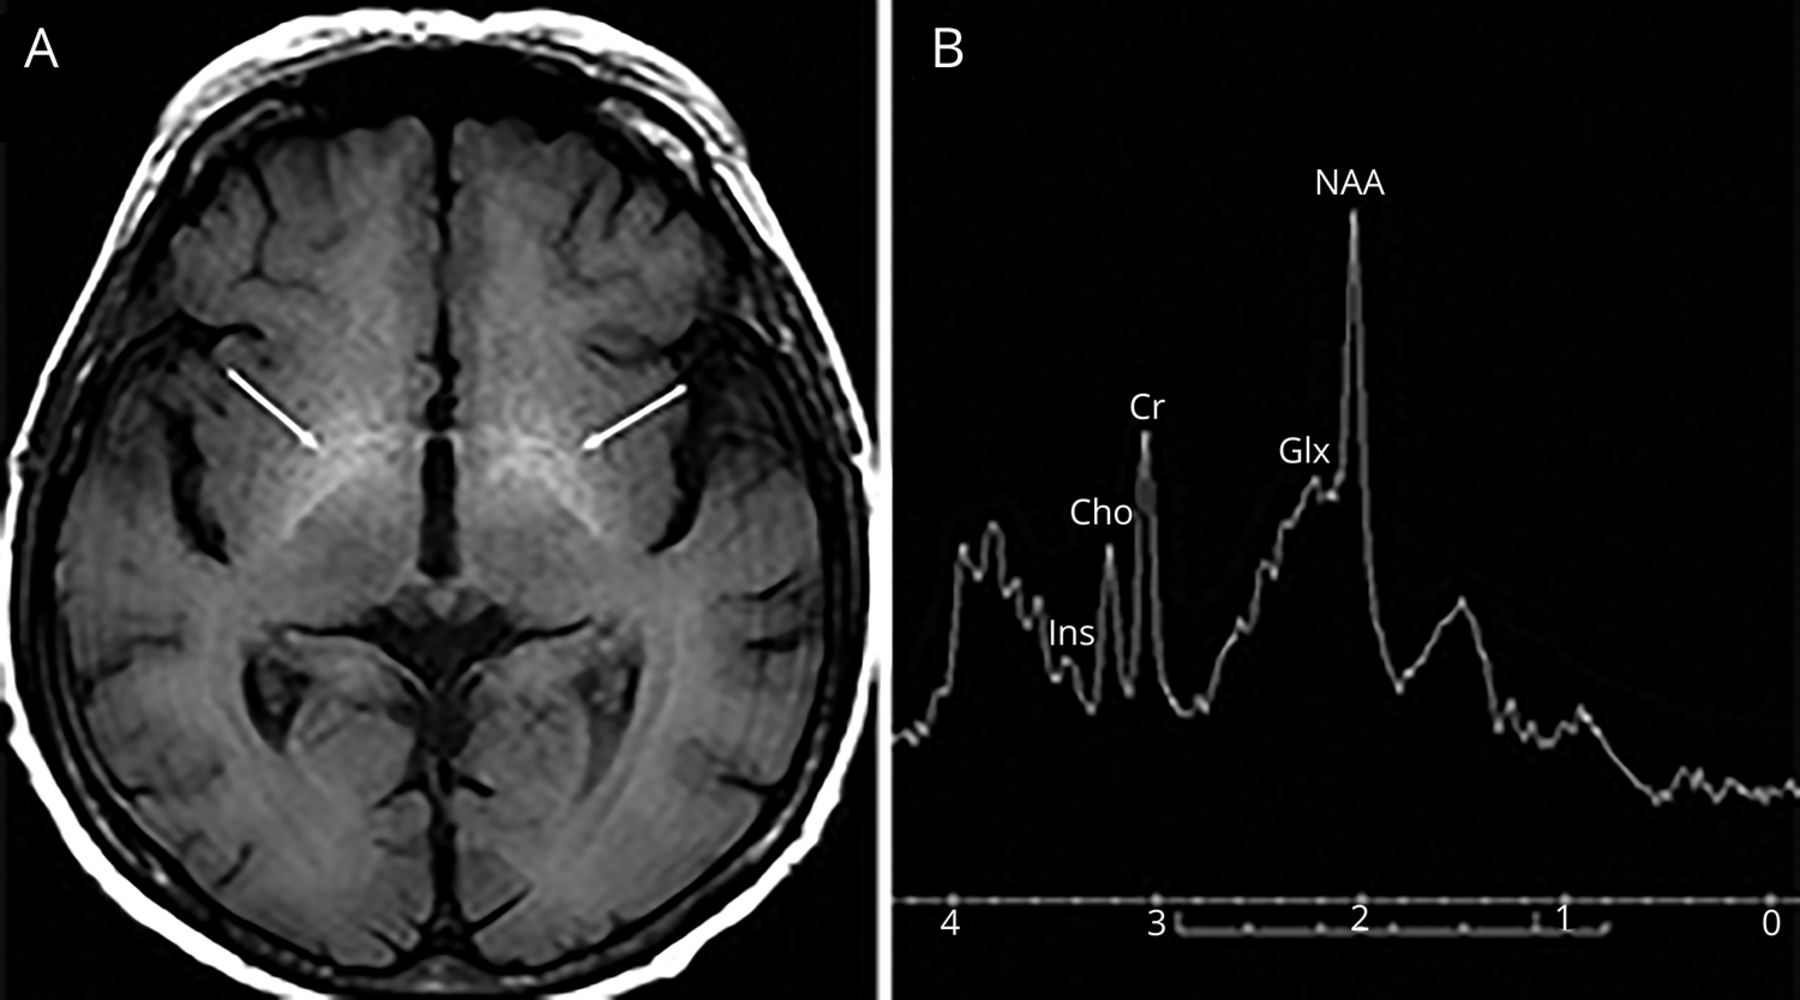

男性,57岁,酒精性肝硬化,有4年肝性脑病(HE)病史,进行性步态障碍,在HE期间加重(视频1).检查发现下肢痉挛和无力。脑MRI显示基底神经节高信号,光谱学显示谷氨酰胺/谷氨酸升高,肌醇降低(数字).脊柱MRI检查正常,排除其他原因。诊断为肝性脊髓病。

(A) t1加权轴向脑MRI显示内苍白球高信号(肝性脑病所致锰沉积[HE])。(B) MRI光谱与位于正常显示的顶叶白质体素的水抑制质子光谱显示谷氨酰胺/谷氨酸信号强度(Glx, 2.15-2.45 ppm)增加,与肌肌醇(Ins, 3.45 ppm)和胆碱(Cho, 3.2 ppm)减少相关。n -乙酰天冬氨酸(NAA)指数信号强度正常(2.0 ppm)。这些发现通常在HE中观察到。